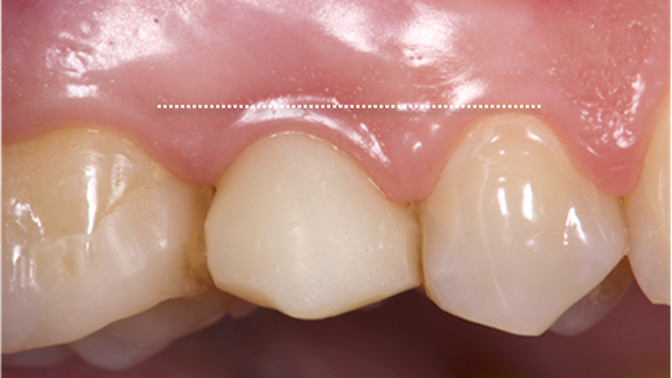

Clinical case: Extraction, immediate implant placement, & provisionalization

- Courtesy of Dr. Iulian Filipov, Romania -

AnyRidge, R2GATE, guided surgery, immediate placement, immediate provisionalization, initial stability, Dr. Iulian Filipov, #25, maxillary posterior, immediate loading, Mega ISQ

AnyRidge implant system, R2GATE, MEGA ISQ, Digital prosthesis